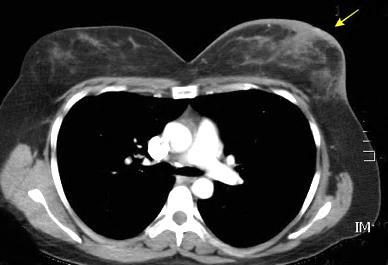

Nódulo en língula.

Cirugía de Ca .de mama hace 23 añosedema de brazo y ganglio en axila. ¡Metástasis!.

Ecanow JS et l. Axillary Staging of Breast Cancer: What the Radiologist Should Know. Radiographics 2013